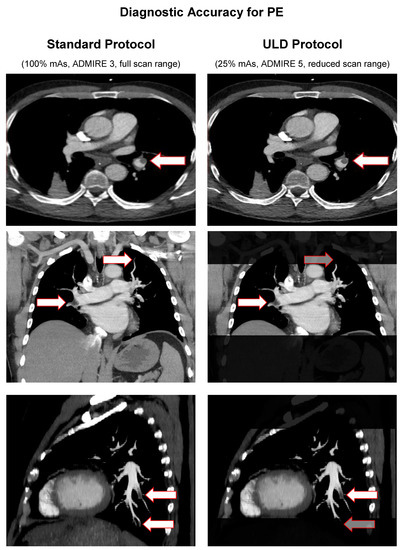

With a maximum of 20 awardable points, standard protocol yielded a mean modified Qanadli score of 8.55 ± 6.271 points vs. ULD protocol with 8.45 ± 6.283 points. Mean severity (the percentage of affected vessels) was 42.74% ± 31.356 in standard protocol and 42.26% ± 31.434 in ULD protocol. Pearson’s correlation showed a strong coherency (r = 0.998, p < 0.001) between the modified Qanadli score measurements, as well as severity in both protocols. Student’s t-test for paired samples showed no significant differences (T = 1.667, p = 0.103) between the modified Qanadli score measurements and consecutively the severity in both protocols. Figure 6 illustrates diagnostic accuracy for PE in our population with example images from three patients for both protocols. Greyed out arrows mark false-negative findings.

Figure 6.

Diagnostic accuracy for PE in standard protocol vs. ULD protocol.